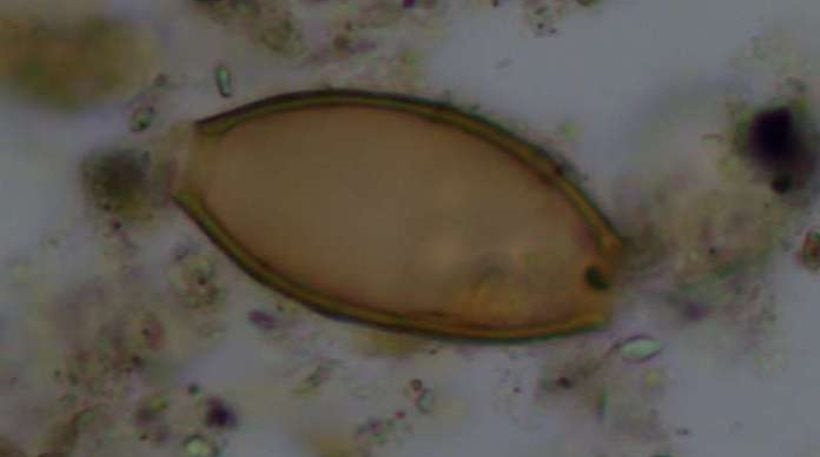

Κέα: Ανακαλύφθηκαν αρχαία κόπρανα με τα παρασιτικά «σκουλήκια του Ιπποκράτη»

Βρετανοί και Έλληνες επιστήμονες ανακάλυψαν αυγά παρασιτικών σκουληκιών μέσα σε αρχαία κόπρανα που βρέθηκαν σε ανασκαφές τάφων στις τοποθεσίες Αγία Ειρήνη και Κεφάλα της νήσου Κέας (Τζιά...